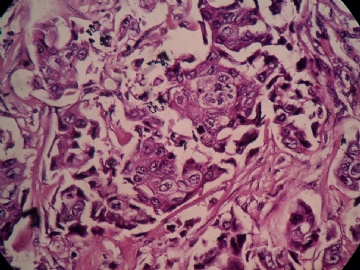

B2778浸润性导管癌?

姓    名: ××× 性别:  女 年龄:  45

标本名称:  左侧近乳晕处肿物

简要病史:  患者描述有疼痛

肉眼检查:  肿物一个2.5*2*1厘米,切面灰白质地硬。

• 浸润性导管癌?图1

图1

• 浸润性导管癌?图2

图2

上皮样细胞,大部分粘附成团成巢,明显浸润。大部分细胞大,核级别高,少数图中见松散的小细胞。未见原位癌。

大细胞考虑浸润性导管癌(3级),小细胞要排除小叶癌。如果有条件请做免疫组化。